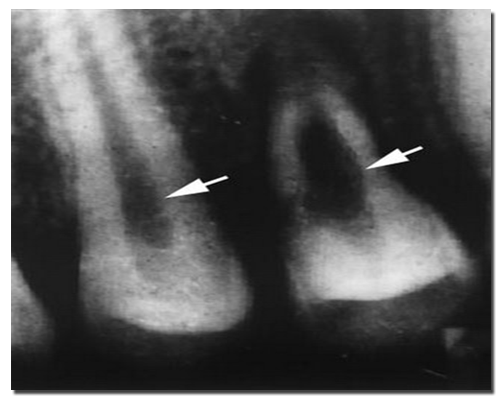

牙内吸收多数发生在单个牙,一般无自觉症状,也可有冷热刺激痛表现。严重牙内吸收者也可表现自发性、阵发性、放射性痛。若吸收发生在冠部,且吸收达表面时,红色肉芽组织可透过薄层牙体组织,使牙冠显示出粉红色斑点。严重的牙内吸收可致患牙穿孔、破损或折断。X线片可见患牙显示圆形或卵圆形透射区,或髓腔呈边缘不规则增大的透射区。

有时可见吸收和修复两种情况同时存在。吸收陷窝部分或全部被修复性牙本质或骨样牙本质所替代,部分病例修复性牙本质或骨样牙本质又可出现再一次吸收。可见牙本质吸收陷窝,内有破骨细胞牙内吸收须经根管治疗去除牙髓内肉芽组织才能使吸收停止。严重牙内吸收甚至穿通牙本质和釉质或牙本质和牙骨质。